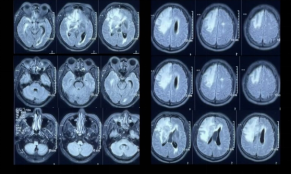

2019年11月,患者因“头痛,无发热、恶心、呕吐,2天好转,反应迟钝,驾车出错”就诊于外院,MRI示双侧大脑半球多发异常信号,右额病灶有占位效应,周围大片水肿(图1),右额病灶环形强化&结节样强化,DWI弥散受限(图2),同期头颅CT示脑实质内散在点状钙化(图3)

图2:右额病灶环形强化&结节样强化,DWI弥散受限